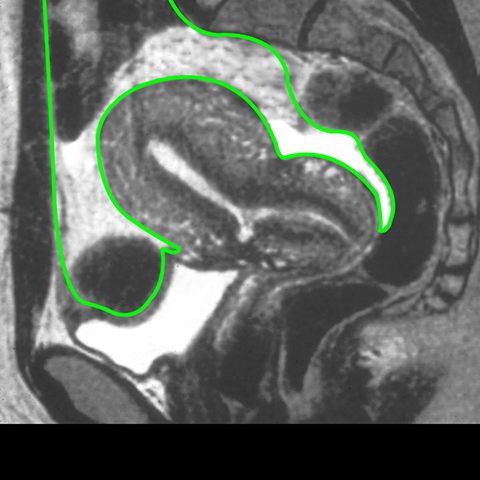

Female Reproductive Organs ( T2 weighted MR, sagittal) [2 of 5]